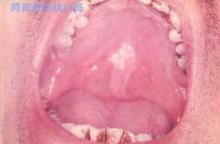

口腔黏膜白斑 口腔黏膜白斑常表現為以下幾種類型:

1.斑塊狀:口腔黏膜上出現白色或灰白色均質型較硬的斑塊,平或稍高出黏膜表面,不粗糙或略感粗糙,柔軟,可無症狀或輕度不適感。

2.顆粒狀:口角區黏膜多見,在充血的黏膜上白色損害呈顆粒狀突起,表面不平,可有小片狀或點狀糜爛,刺激痛,本型白斑多數可查到白色念珠菌感染。

3.皺紋紙狀:多發生於口底及舌腹,表面粗糙,邊界清楚,周圍黏膜正常,白斑呈灰白色或堊白色,患者除粗糙不適感外,初起無自覺症狀,亦可有刺激痛等症狀。

4.疣狀:損害呈乳白色,厚而高起,表面呈刺狀或絨毛狀突起,粗糙,質稍硬,多發生於牙槽嵴、唇、上齶、口底等部位。

5.潰瘍狀:在增厚的白色斑塊上,有糜爛或潰瘍,可有或無局部刺激因素,可有反覆發作史,疼痛。口腔黏膜白斑的好發部位為頰,唇次之,舌、口角區、前庭溝、齶、牙齦也有發生,雙頰白斑最多見,往往位於咬合線處,寬約1cm左右,有的延及口角。在口角1cm處為唇聯合區,該區白斑應警惕惡變,特別是伴有白色念珠菌感染者。